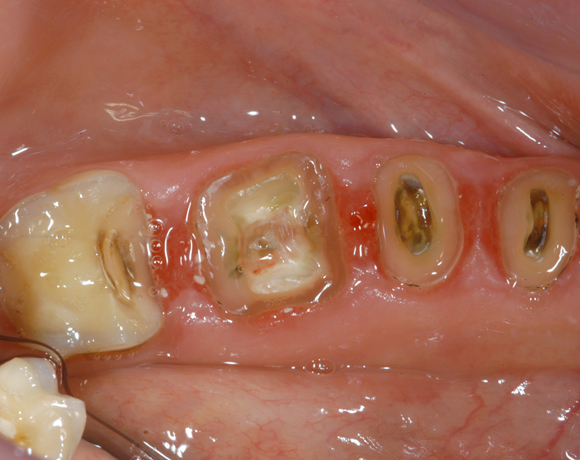

22 Einzelkronen mit Eris for E II

Empress II Presskeramik mit Eris Verblendkeramik bei einer Neuversorgung im Oberkiefer komplett und im Unterkiefer Vollkronen auf den Seitenzähnen.

Ein Projekt aus dem Jahr 2004

Hier wurden der ganze Oberkiefer und die Seitenzähne im Unterkiefer mit neuen Kronen aus Empress 2 und mit Eris Verblendkeramik versorgt.